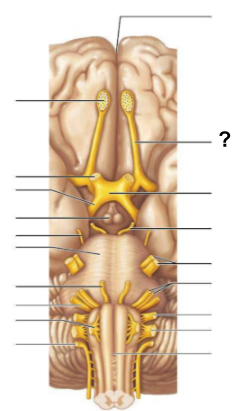

What structure, labeled “?”, is the starting point of cerebrospinal fluid circulation in the brain?

Lateral ventricle